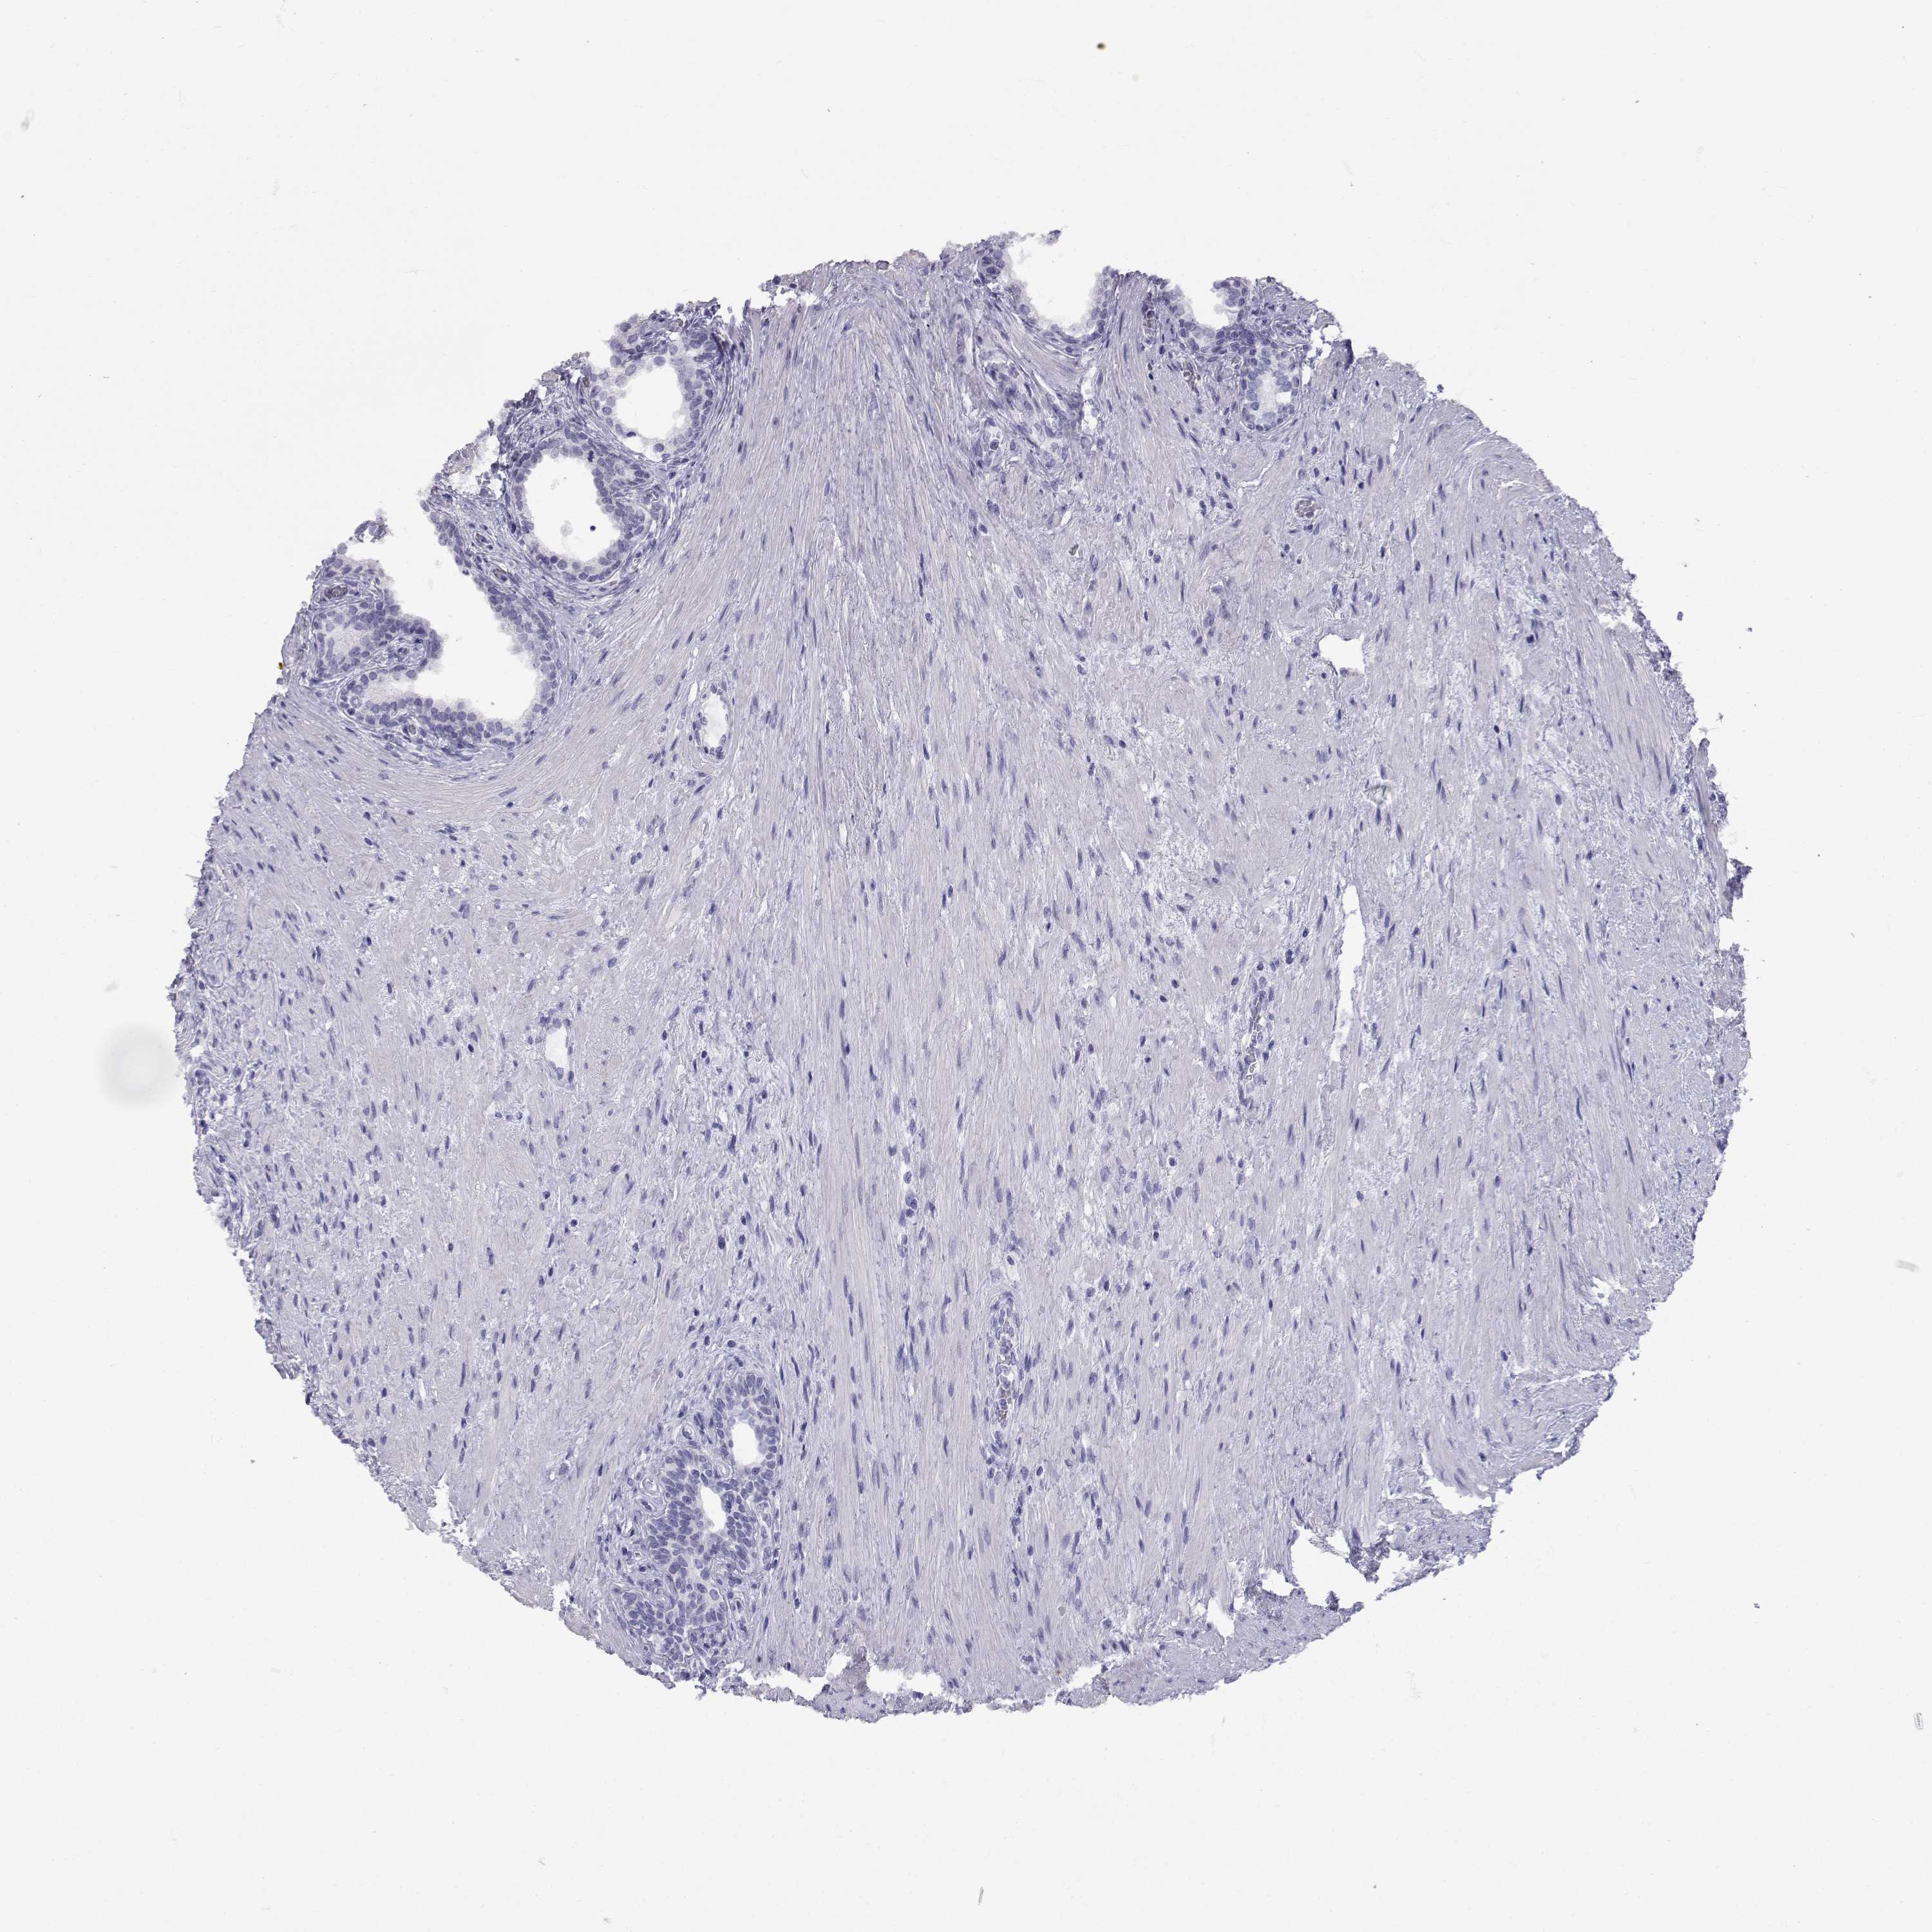

PROSTATE CANCER - Protein expressioni

A mouse-over function shows sample information and annotation data. Click on an image to view it in a full screen mode. Samples can be filtered based on level of antibody staining by selecting one or several of the following categories: high, medium, low and not detected. The assay and annotation is described here.

Antibody stainingi

Antibody staining in the annotated cell types in the current human tissue is reported as not detected, low, medium, or high, based on conventional immunohistochemistry profiling in selected tissues. This score is based on the combination of the staining intensity and fraction of stained cells.

Each image is clickable and will lead to virtual microscopy that enables deeper exploration of all samples and also displays staining intensity scores, fraction scores and subcellular localization as well as patient and tissue information for each sample.

Antibody HPA012763

Adenocarcinoma, Medium grade